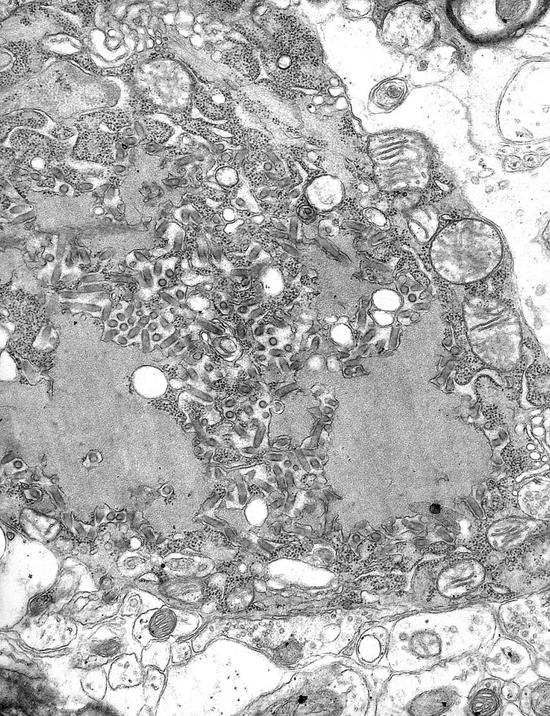

这些疫苗是把致病的病毒或细菌分离出来,在严格的条件下做体外培养和扩增,然后采用生物学、物理或化学的方法将它们杀死或使它们的毒力降低,再与可增强免疫反应的佐剂混合,最后接种注射到人体。

这些灭活或减毒的病原微生物在人体内不能增殖和释放各种有害物质,所以不会引起疾病;但它们携带的各种抗原可以被我们身体的免疫系统识别,诱导出特异性的抗体。当人们被这些病原感染后,这些抗体自己或它们与免疫细胞协同就可以将这些病原微生物杀死。